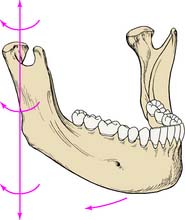

As for any other movement in space, complex three-dimensional mandibular movement can be broken down into two basic components: translation, when all points within a body have identical motion, and rotation, when the body is turning about an axis (Fig. 4-5). Every possible three-dimensional movement can be described in terms of these two components. It is easier to understand mandibular movement when the components are described as projections in three perpendicular planes: sagittal, horizontal, and frontal (Fig. 4-6).

Fig. 4-5 Three-dimensional movement of a body can be defined by a combination of translation (all points within the body having identical movement) and rotation (all points turning around an axis).